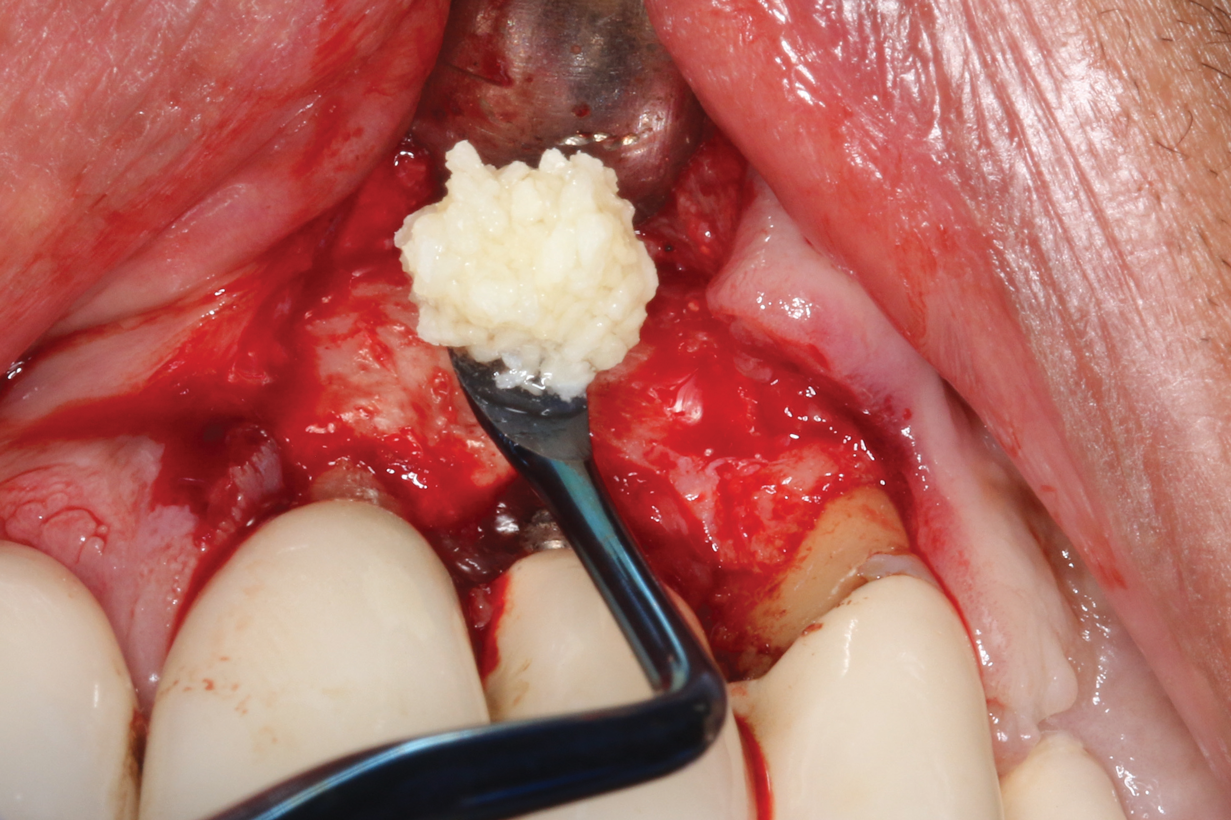

Following infiltration of the facial attached gingiva and palatal area with articaine hydrochloride 4% and epinephrine 1:100,000 (Septocaine®, Septodont [alternatively: Articadent®, Dentsply Sirona; Orabloc®, Pierrel]), an envelope releasing incision was made extending one full tooth over. To prevent trauma to the mucosal tissue, vertical incisions were not made (Figure 3). Incising the mucosa results in the release of prostaglandins and histamine, which increases postoperative discomfort. For this patient, staying in attached gingiva provided excellent control of the flap and allowed clear access to the apical lesion.

There are many grafting materials available today, including allografts (from a human source), xenografts (from another species), and alloplasts (from synthetic materials).23 Following debridement and sterilization of the apical lesion, the site was grafted with a mineralized cortical/cancellous bone allograft material (Newport Biologics Mineralized Cortico/Cancellous Allograft Blend, Glidewell Direct [alternatively: OSSIF-I sem Mineralized Cortical/Cancellous Bone Allograft, Surgical Esthetics; enCore® 50/50 Cortical & Cancellous Allograft, Osteogenics]). The material was packed firmly around the entire implant body but not crushed (Figure 7). Next, a resorbable collagen membrane (Newport Biologics Resorbable Collagen Membrane 3-4, Glidewell Direct [alternatively: Bio-Gide®, Geistlich Biomaterials; BioMend®, Zimmer Biomet]) was trimmed to extend approximately 2-mm beyond the borders of the defect and then passively positioned to serve as a barrier against epithelial growth during the healing and remodeling phase (Figure 8). A sling suture technique using polyglactin 910 suture was then used to reposition the envelope reflection (Figure 9 through Figure 11). Polyglactin 910 suture is a smooth, synthetic, absorbable, braided suture made of polyglycolic acid that is broken down over time by hydrolysis. This suture material reduces the inflammatory response that can be observed with other suture materials.

(3.) An envelope reflection was made with no vertical incisions, exposing the entire bony defect affecting the apical portion of the stable implant.

Figure 3

(7.) Allograft was firmly packed around the implant body without crushing the material.

Figure 7